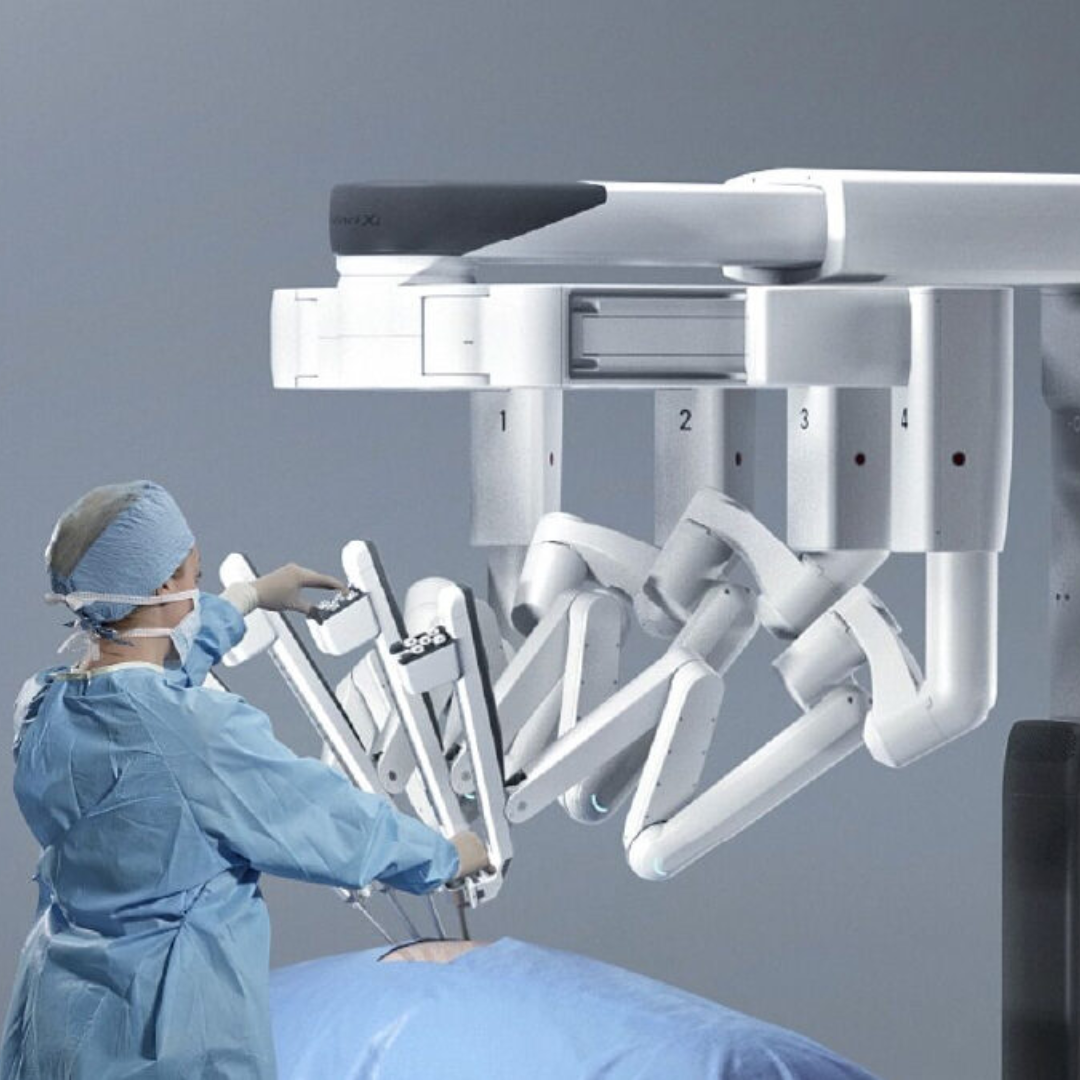

A evolução da medicina é constante, com muitos procedimentos cirúrgicos hoje em dia sendo realizados por via videolaparoscópica e robótica. Nossos urologistas são verdadeiros entusiastas da cirurgia minimamente invasiva.